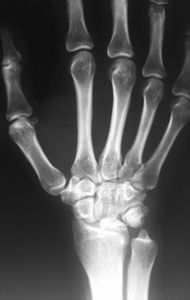

Providing specialist treatment for hand and wrist conditions in Shropshire and the surrounding area

A wide variety of conditions can affect the hand and wrist causing pain, deformity, numbness and loss of function. If you are concerned it is always best to have this assessed professionally as it is not always straightforward to make a diagnosis. Information about some of the more common conditions and treatments can be found in the menus above.